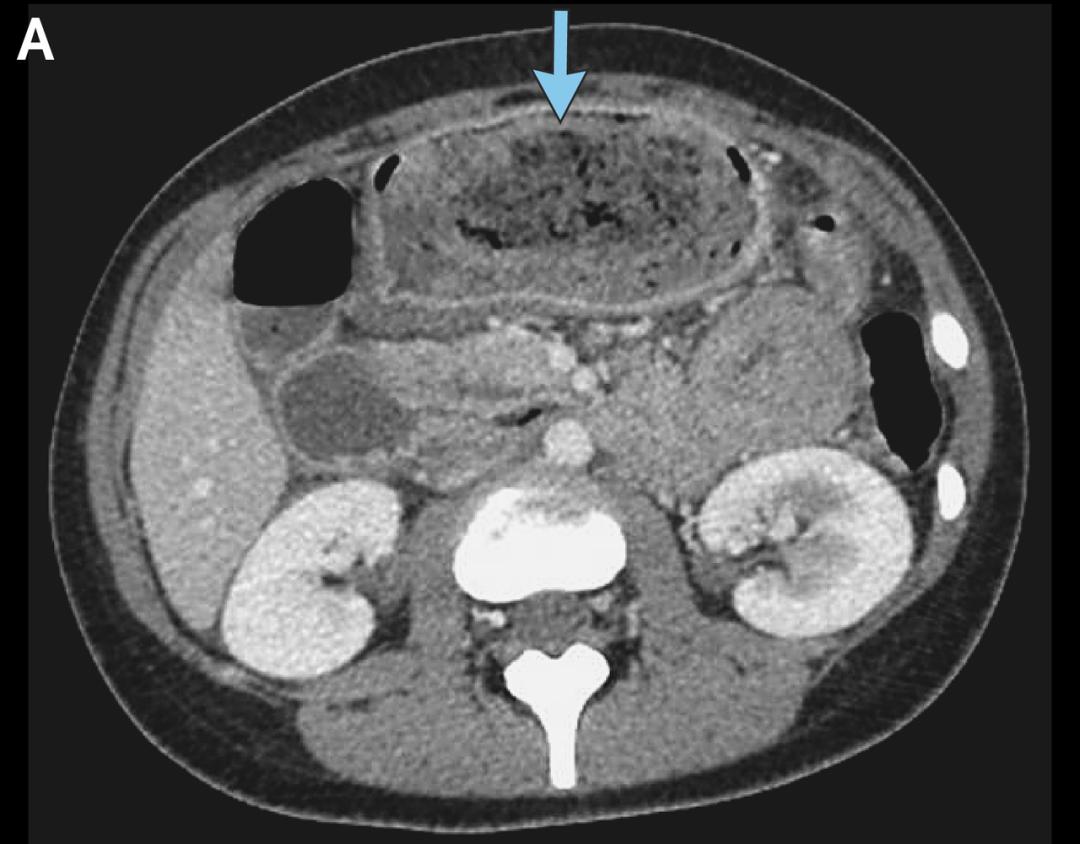

左滑查看更多图片:胃石示意图、手术中看到的毛发性胃石、CT检查中的胃石 | 参考文献[1]

[1]Crane MA, Economos NG, Vaidya A, Apovian CM, Rodriguez NJ. A Fizzy Fix. N Engl J Med. 2025 Sep 25;393(12):e20. doi: 10.1056/NEJMimc2502450. PMID: 40991904.